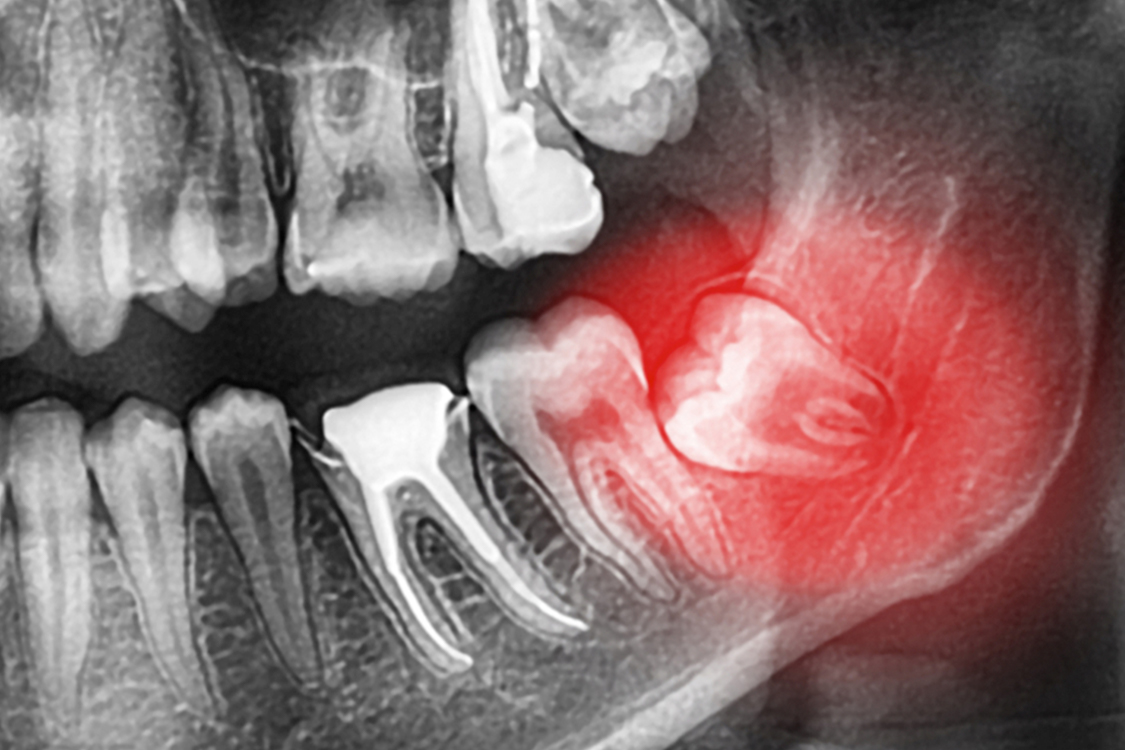

Kist Operasyonları

Kist oluşumuyla alakalı meydana gelen operasyonlar çene bölgesinin herhangi bir kısmında yapılabilmektedir. Kist oluşumları özellikle kist operasyonları yardımıyla ortadan kaldırılabilir. Çene yapısını olumsuz etkileyen bu durum fark edildikten sonra kısa süre içerisinde ameliyatla yok edilmesi gerekir.